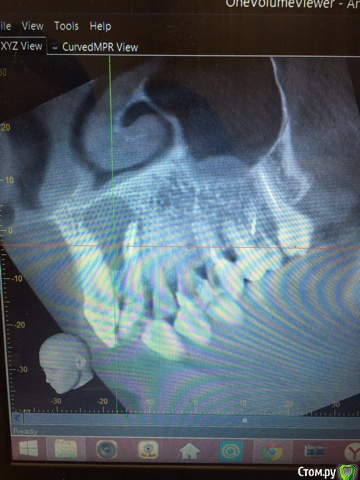

Анна калякина Опубликовано 4 июня, 2017 Поделиться Опубликовано 4 июня, 2017 Здравствуйте! Очень нужна помощь стоматологов!!! Пожалуйста помогите советом!!!В феврале 2017 года на рентгене обнаружена киста корней зубов 21,22После КТ хирург посоветовал удаление двух зубов, терапевт предложил попробовать лечении через канал, за это время меняли лекарство 4 раза ( антисептик и кальций)Каждый раз после введения лекарства десна припухает, в течении месяца отек спадает, но снова меняем лекарство и десна над зубами увеличивается...Лекарство вводим через 22, 21 зуб живой.Пожалуйста посоветуйте что делать дальше. Спустя 3 месяца по рентгену улучшений нет(Спасибо! 1 Ссылка на комментарий